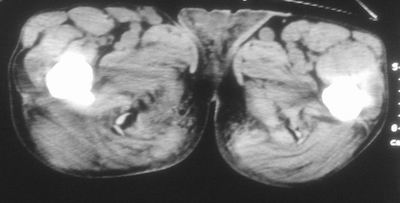

标题: CT16837:M63Y,右臀部巨大软组织包块 [打印本页]

标题: CT16837:M63Y,右臀部巨大软组织包块

患者,男,63岁,自诉3个月前发现右臀部包块,触及疼痛,治疗后缩小。前天突然增大。无高热病史。

病灶内部可见出血,首先考虑急性出血性病变.血肿?

给个骨窗,判断一下肿块是否与髂骨有关,肿块内出血是肯定的,至于是感染形成的脓肿还是起源于肌肉或纤维组织的肉瘤则难以确定,不过从影像上看,包膜完整,且环形增厚,病灶下部见斑片状底密度坏死,个人倾向感染可能性大

肌间隙明显混浊,三个月前治疗有缩小,支持考虑臀大肌下脓肿伴出血,肿瘤如果出现瘤内出血的话瘤外边界应该较清楚,现在表现为一种恶性征像,但骨质无明显异常,且臀小肌边界清楚,不符合恶性表现.